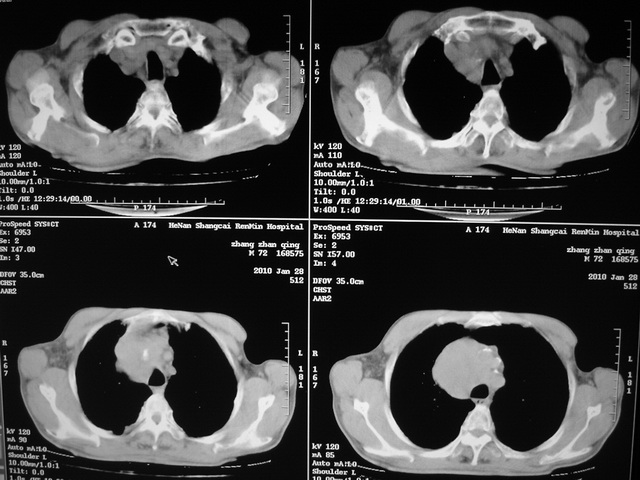

xx m 72岁农民 右侧胸痛6月余,咳嗽,无发热、咯血等

右下周围型肺癌,并右肺门、纵膈淋巴结、内乳淋巴结转移,右胸膜转移累及前胸壁。鉴别:脓肿、tb、淋巴瘤。病理类型可能为大细胞型。

这个病人有点复杂了,上纵隔像是占位,右肺下叶见壁光整厚壁空洞加液平,像是肺脓肿,中叶病灶牵涉到胸膜及胸壁,形态看像是炎性病变,总之不能除外恶性病变,还是穿刺或增强后再说。

支持2搂,考虑右肺下叶周围性肺癌伴肺门及纵膈淋巴结转移!右侧前纵膈病灶,还是一元论考虑为胸壁或胸膜转移瘤。

右侧周围性肺癌,胸膜转移。